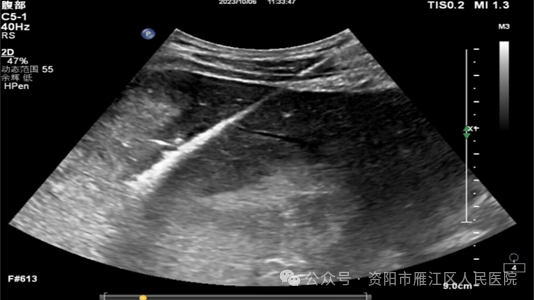

近日,56岁的李大叔因“右上腹疼痛20+天”入住我院。入院后查腹部增强CT:肝脏内结节、团块状稍低密度影,考虑肿瘤性病变。遂请超声科会诊, 腹部普通肝脏彩超提示:肝右叶实性占位,考虑肿瘤性病变可能。

为进一步明确肝右叶病变的病理类型,遂行超声引导下肝肿物穿刺活检:

穿刺过程十分顺利,术后患者恢复良好,无明显不适症状。穿刺活检术后病理结果:考虑为低分化肝细胞癌(WHO III级)。为制定下一步治疗方案提供了重要依据。